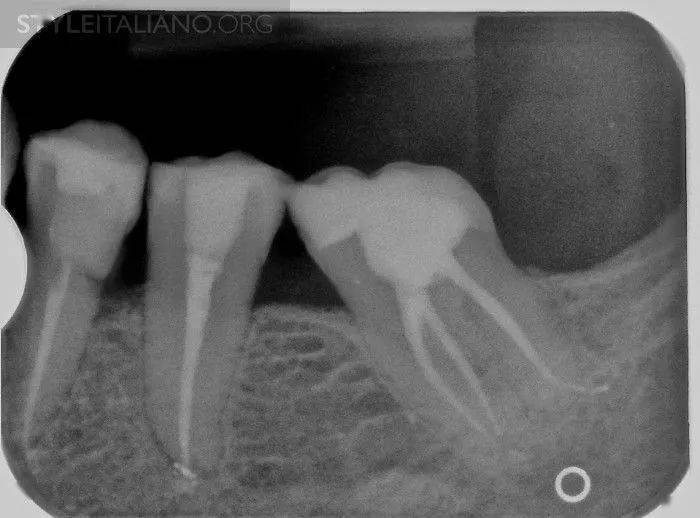

【病例讨论】上午一例复杂的47一次性根充 [病例帖]

口腔医院专家解读图1中远中根充至根尖2mm以内,属于恰填范围,且根管